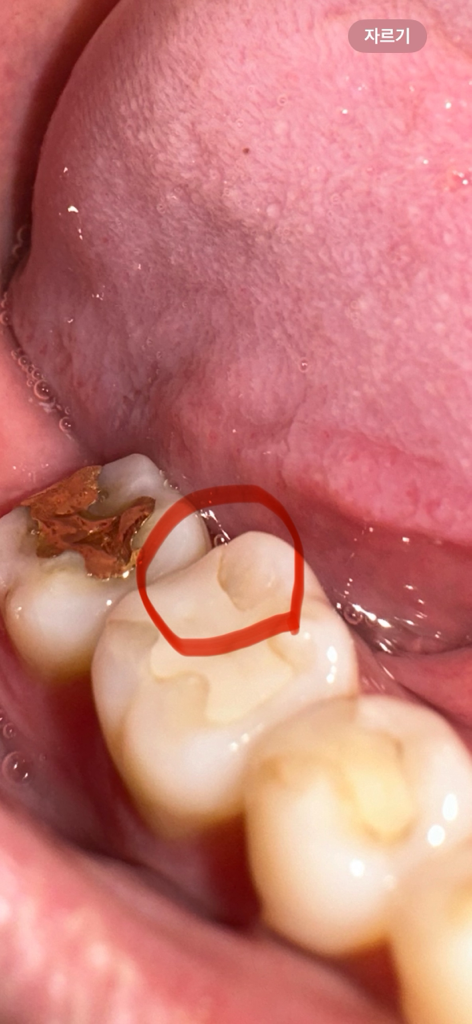

이게 충치가 확실한걸까요? 벌어졌어요 ㅠㅠ

보철물이랑 치아 사이 틈이 생겼어요.. 눈으로만 봐도 충치인게 확실한걸까요? 한번씩 가끔 음식 씹을때 찌릿하곤 해요 ㅠㅠ 눈으로만 봐도 심각한가요?.. ㅜㅜ 무조건 보철물 교체를 해야하는거죠? 다음주 금요일에 치과 방문이 가능한데 그 기간동안 충치가 더 심해질까요? ㅠㅠ

• 1번 째 사진